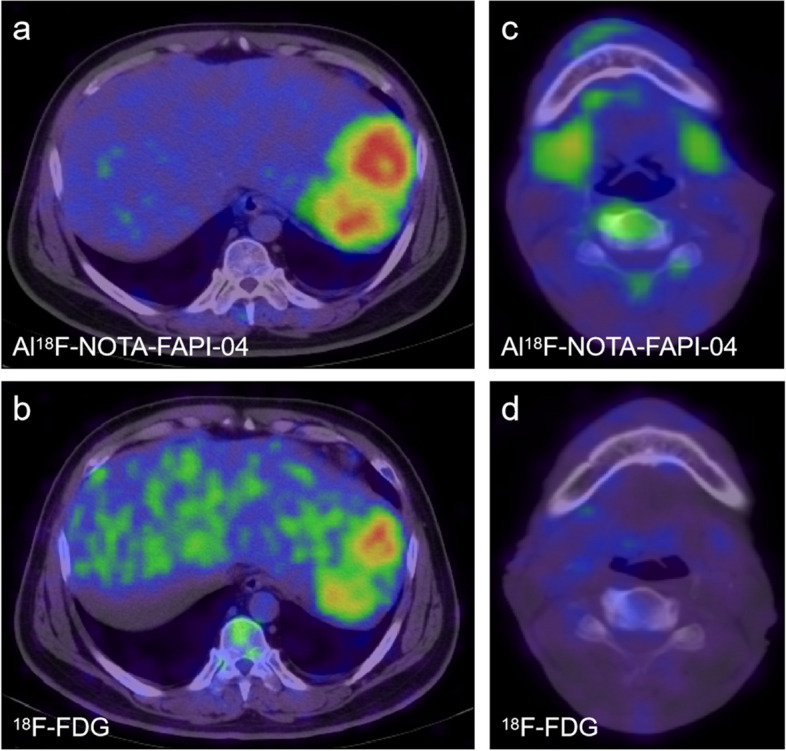

Al18F-NOTA-FAPI-04 PET/CT and 18F-FDG PET/CT have similar detection abilities for primary pancreatic tumors in this cohort, however, Al18F-NOTA-FAPI-04 PET imaging showed a higher radioactive concentration (Fig. 3A). The mean level of SUVmax-15min, SUVmax-30min, and SUVmax-60min uptake of PDAC lesions in the Al18F-NOTA-FAPI-04 tracer were 9.7 ± 2.0, 10.4 ± 2.3, 10.3 ± 2.4, respectively, and the 18F-FDG tracer was 4.1 ± 2.2 (all P < 0.01); the mean level of SUVmean-15min, SUVmean-30min, SUVmean-60min in Al18F-NOTA-FAPI-04 tracer were 4.5 ± 1.1, 4.4 ± 1.4, 4.4 ± 1.1, respectively, and the 18F-FDG tracer was 2.0 ± 1.0 (all P < 0.01) (Fig. 3B). The mean TBR1 quantitative measurements of the 15-min Al18F-NOTA-FAPI-04 tracer was 6.9 ± 2.5, and that of the 18F-FDG tracer was 2.6 ± 1.3 (P < 0.01), the mean quantitative measurements of TBR2 in 15-min Al18F-NOTA-FAPI-04 tracer was 6.2 ± 2.7, and the 18F-FDG tracer was 1.5 ± 0.7 (P < 0.01), the mean quantitative measurements of TBR3 in Al18F-NOTA-FAPI-04 tracer was 6.4 ± 1.9, the 18F-FDG tracer was 5.4 ± 2.8 (P = 0.091) (Fig. 3C).

Fig. 3.

a. Female, 62 years old, comparison of Al18F-NOTA-FAPI-04 and 18F-FDG uptake values in PDAC. Compared with FDG, FAPI PET imaging showed the lesions in the head of the pancreas clearly with higher TBR. The image quality of 15-minute, 30-minute, and 1-hour imaging can satisfy the diagnostic requirements (SUVmax: 12.9, 12.7, 10.1), where no uptake of FDG showed(SUVmax: 1.8). b. c. The SUVmax, SUVmean, TBR1, TBR2, and TBR3 values of Al18F-NOTA-FAPI-04 PET / CT imaging were significantly higher than those of FDG